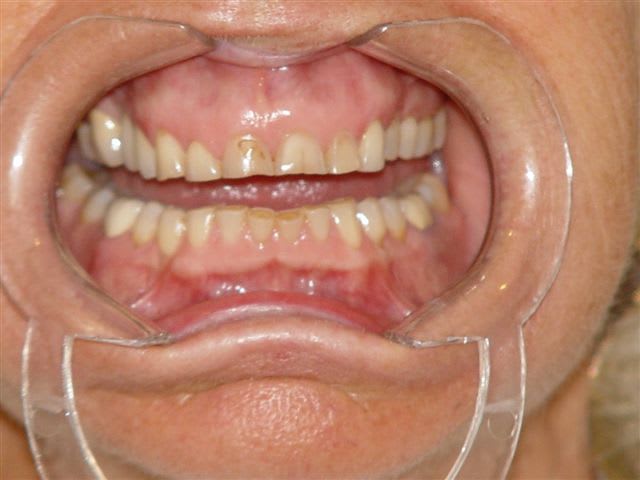

pour info et sans chirurgie, juste avec un machouilleur et le cerec

Perte de dvo laf6bw - Eugenol

Dvo à restaurer qjd6xd - Eugenol

Ainsi ntouaf - Eugenol

Cerec et e max xh3pat - Eugenol

Quand on voit l'usure des dents et la dvo actuelle, on peut tenter de réhausser les dents en désocclusion par des onlays comme je l'ai montré ci dessus, d'autant plus qu'à 78 ans le grand père de fluornet ne doit pas mourrir d'envie de repasser sur le billard avec un pronostic plus qu'alléatoire à mon humble avis, mais je pense que tout le monde a compris que je ne suis pas la diva du bistouri ce que je revendique haut et fort, les résultats de la dentosophie étant souvent bien plus satisfaisants que ceux des interventions chirurgicales maxillofaciales lourdes.